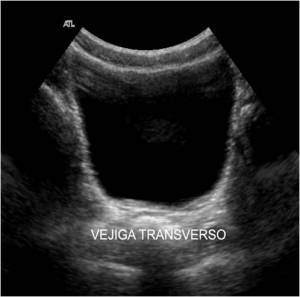

Lo primero y más importante, para atender convenientemente una petición de estudio de la Próstata lo que tenemos que tener es una vejiga lo suficientemente llena para poder valorarla bien. Una vejiga mal repleccionada puede darnos problemas, pero una vejiga excesivamente repleccionada, también, el paciente puede estar incómodo y sobre todo, una replección excesiva puede comprimir la glándula y desplazarla y no podremos estudiarla bien.

En ocasiones deberemos pedir al paciente que beba agua y no orine para poder realizar el estudio correctamente.

Al rellenar la Vejiga, lo que conseguimos es una «ventana» para visualizar mejor estructuras como las Próstata que están muy escondidas, por profundidad o por colocación Anatómica. Por eso es indispensable una buena preparación del paciente. Se consigue gracias al aumento de transmisión favorecido por espacios puramente acuosos, como la vejiga llena de orina La interacción del haz ultrasónico y la materia lo explica bien.

Además de una vejiga suficientemente repleccionada, necesitamos esquivar el Pubis, anterior a la Próstata, para eso tendremos que realizar una angulación, que estará en función de cada paciente, para poder acceder a la glándula correctamente tanto en transverso como en longitudinal, que son los dos planos que necesitamos para hacer la medida de la Próstata en los tres ejes de espacio para obtener un volumen de la estructura.

Para llegar a ver la Próstata, con el paciente debidamente preparado, vamos a localizar un corte transverso de la Vejiga y cuando la veamos, realizaremos la angulación arriba mencionada para llegar a la Próstata, este paso es el más complicado técnicamente, pero aquí reside el éxito de la exploración, mira, he hecho un dibujo para explicarlo: